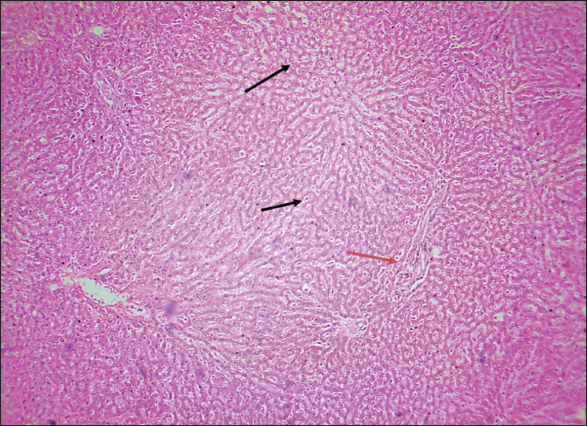

Fig. 6. Histological section of the liver of rats drenched with 0.6 mg/kg citalopram. The section shows a mild fatty degenerative lesion in hepatic tissue characterized by the infiltration of fat droplets inside hepatic cells, which give them a ring-shaped appearance due to pushing the nucleus on the side from the hepatic cells (black arrows). The section shows infiltration of structureless, homogenous, and pinkish material (amyloidosis, red arrow) (H and E stain 100X).

The results of this study revealed no significant differences in bilirubin levels in all treated animals (Table 1), whereas serum ALT and AST levels showed significant elevations in all treated animals either by citalopram alone (fourth group) or with J. regia pulp extract at doses of both 10 and 20 mg/kg (Tables 2 and 3). Sections of histopathological study appeared as mild degenerative lesions characterized by infiltration of fat droplets inside hepatic cells, which gave them a ring shape appearance due to pushing the nucleus at one side from the hepatic cells with fibrous networks formation in the tissue parenchyma, infiltration of structureless, homogenous, and pinkish material (Figs. 16). Clear hepatic vein congestion and narrowing in the hepatic artery and arteriole diameters revealed that citalopram caused liver dysfunction and injury (Figs. 79).

These results correspond with those of other studies, in which patients treated with antidepressants appeared to have moderately elevated levels of the aminotransferase. All antidepressants caused hepatotoxicity; citalopram is that have the least potential for hepatotoxicity, which is characterized by high alanine aminotransferase levels (Gartlehner et al., 2008; Voican et al., 2014; Ilgın et al., 2020). The results of this study revealed no significant differences in bilirubin levels in all treated animals as the level of p < 0.05, serum ALT and AST levels showed a significant elevation in all treated animals either by citalopram only (fourth group) or with J. regia pulp extract at doses of 10 and 20 mg/kg B.W. Sections of histopathological sections show mild degenerative lesions characterized by infiltration of fat droplets inside hepatic cells, which give them a ring shape appearance due to pushing the nucleus at one side from the hepatic cells with fibrous networks formation in the tissue parenchyma, infiltration of structureless, homogenous, and pinkish material (Figs. 4 and 6). Clear hepatic vein congestion and narrowing in the hepatic artery and arteriole diameters revealed that citalopram caused liver dysfunction and injury (Figs. 79).